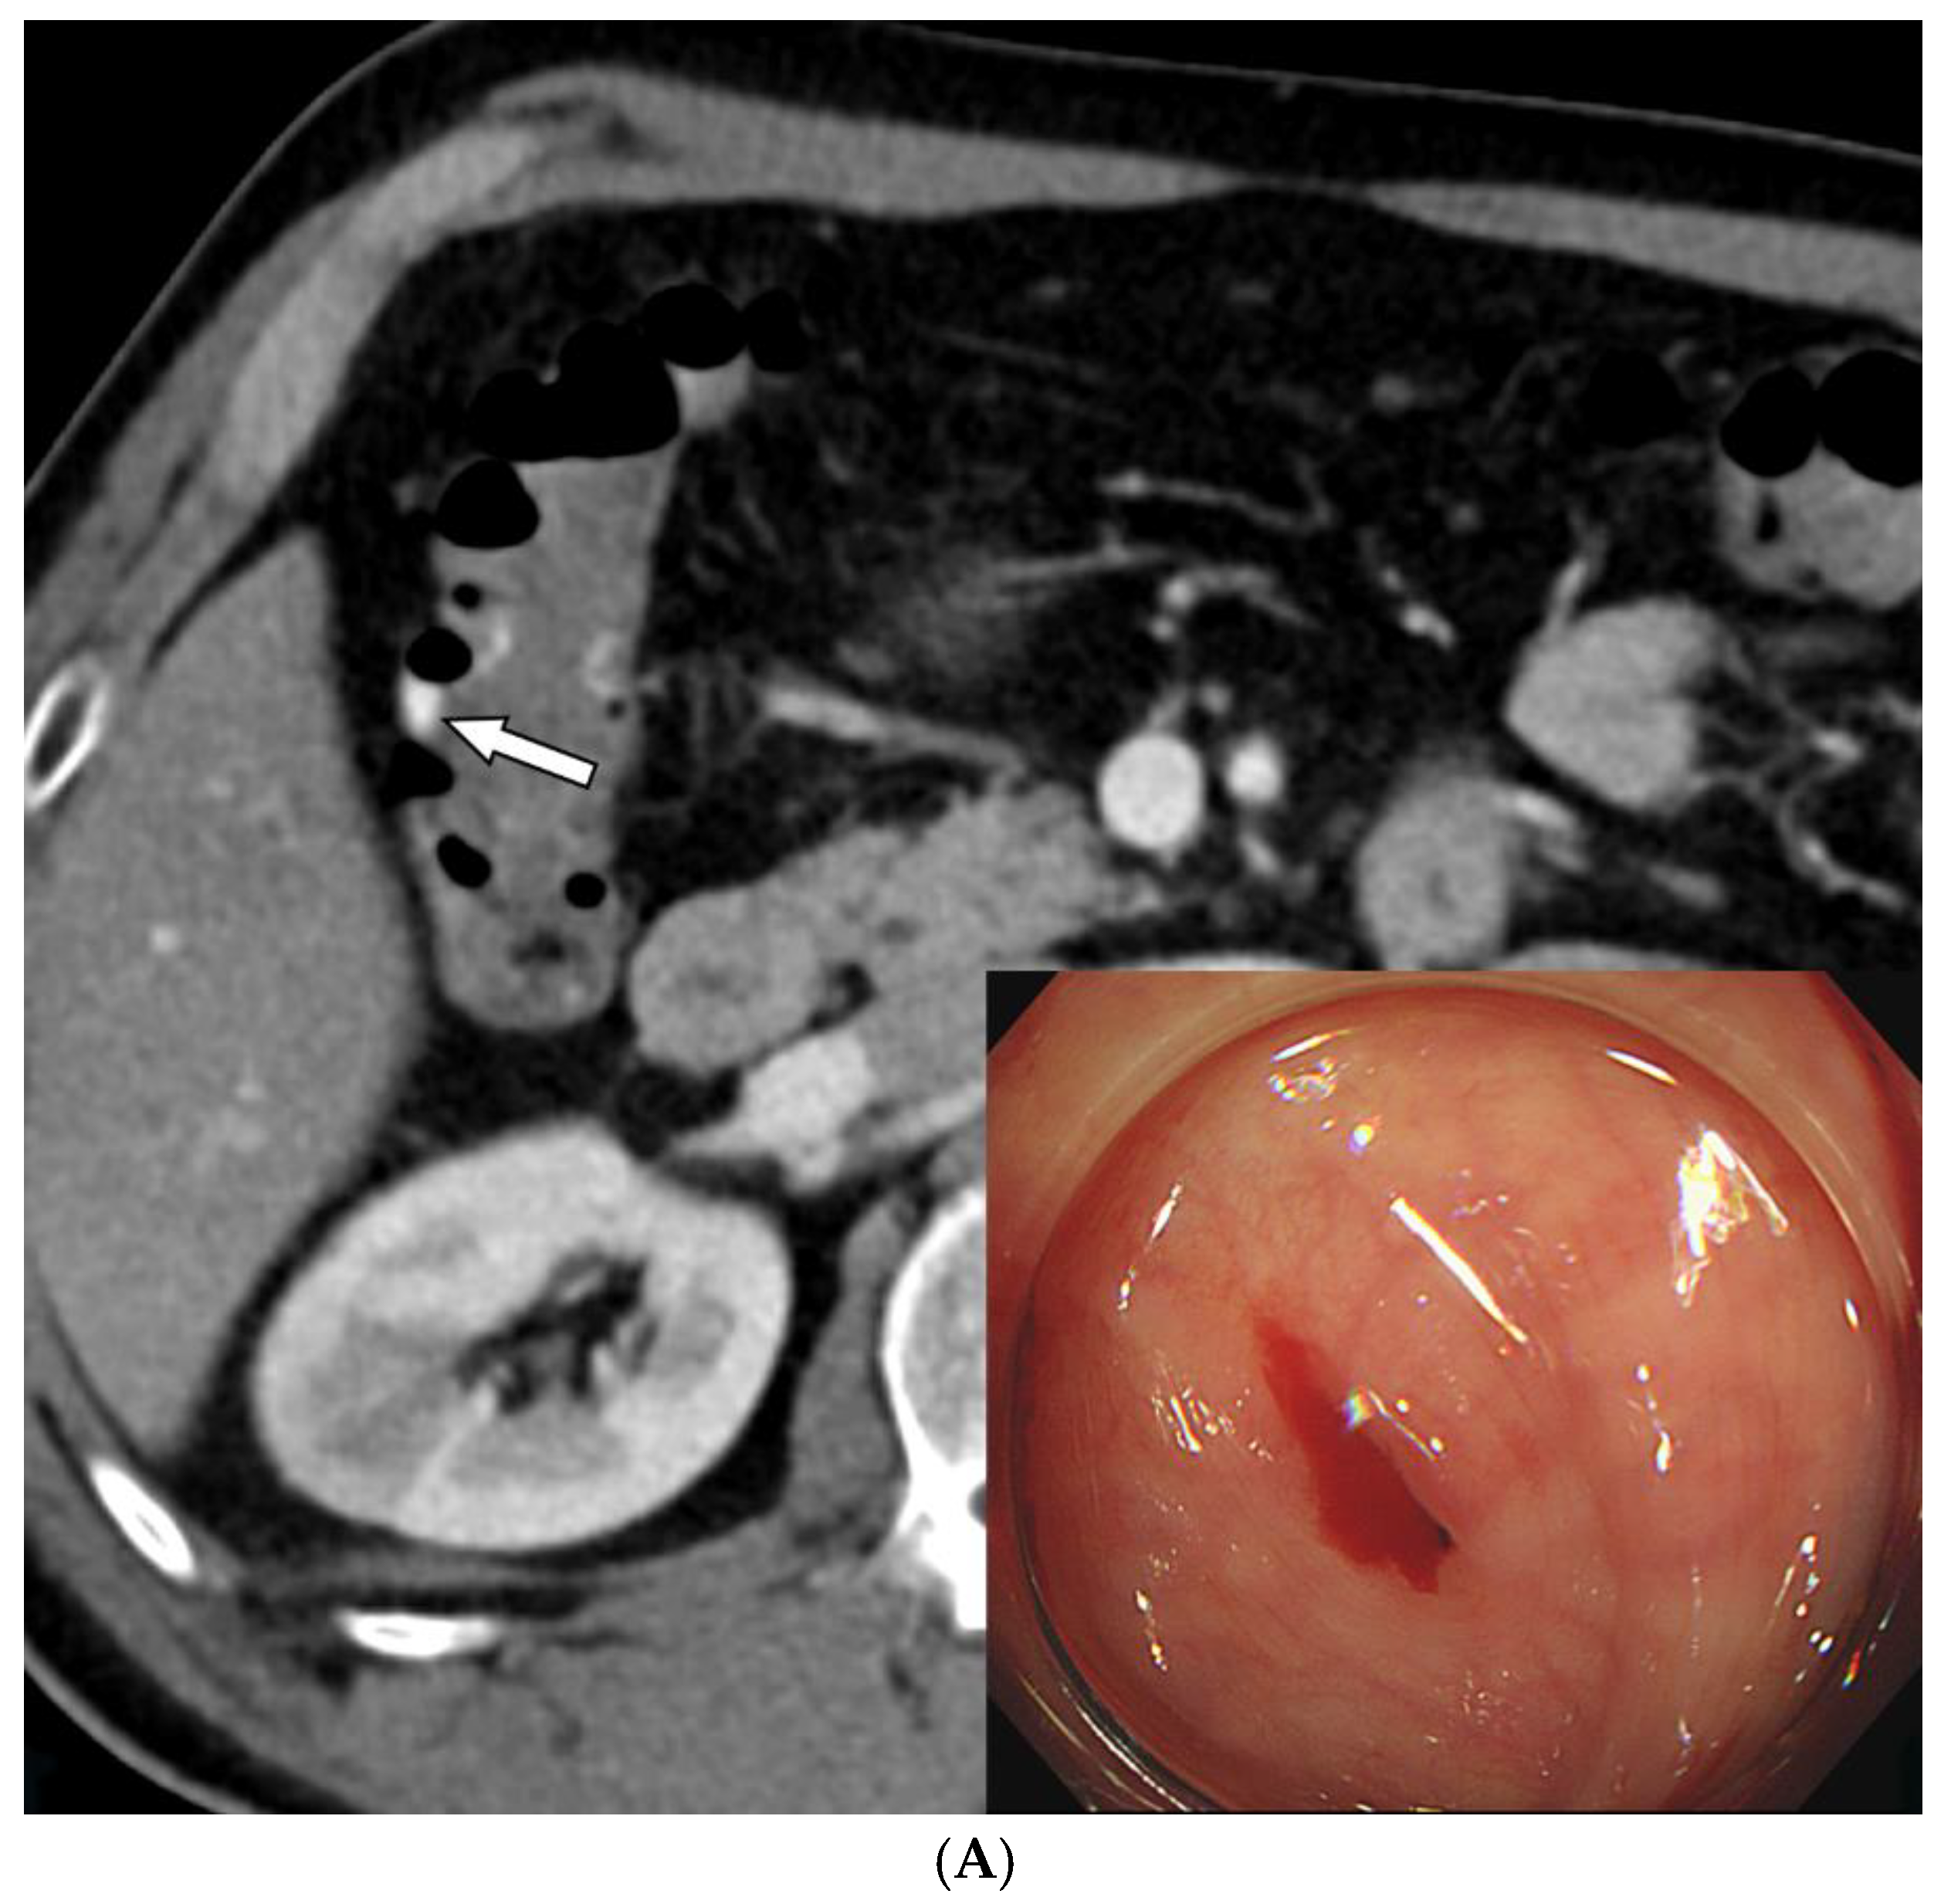

Figure 3. A 59-year-old man with colonic diverticula presented with hematochezia. (A) Contrast-enhanced axial CT image shows colonic diverticula with luminal contrast extravasation (arrow) at the hepatic flexure. Sigmoidoscopy performed one day after the CT scan reveals a diverticulum with bleeding (inset). Endoscopic hemoclipping was performed (not shown). (B) Superior mesenteric arteriography demonstrates focal hypervascularity (arrows) around the endoclipping site, without evidence of contrast extravasation. As superselection was not possible, the arterial branches leading to the endoclipping site were embolized using quick-soluble gelatin sponge particles (150–350 µm). (C) Post-embolization arteriography shows marked reduction in the previously observed hypervascularity around the endoclipping site. (D) Sigmoidoscopy performed two days after embolization reveals several ulcers and erythematous changes around the hemoclipping site, consistent with ischemic colitis. Associated abdominal pain resolved within three days. No further bleeding occurred during the 6-month follow-up.